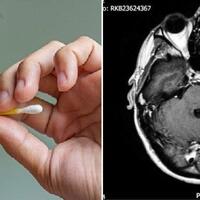

Pria Inggris Menderita Infeksi Otak Mematikan Setelah Gunakan Cotton Bud Sembarangan